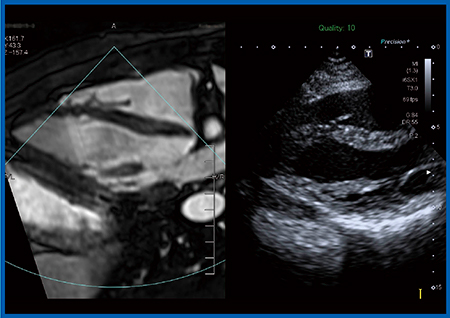

TAVIの実施に当たり,当院では心臓外科医が穿刺する直前に術中エコーにてリアルタイムに心尖部の位置を確認する。しかしながら,本症例は,呼吸機能障害により左肺が過膨張となっており,心尖部が肺の後ろに隠れてしまうため,体位変換が困難な術中には心尖部の描出ができなかった。そこで,Fusion Imagingにて術前のCT画像とリアルタイムの超音波画像を同一画面上に並べて同期表示したところ(図2),心臓外科医も納得し,自信を持って穿刺を行うことができた。

図2 症例:Fusion Imagingによる術前CT画像と術中超音波画像の同期表示